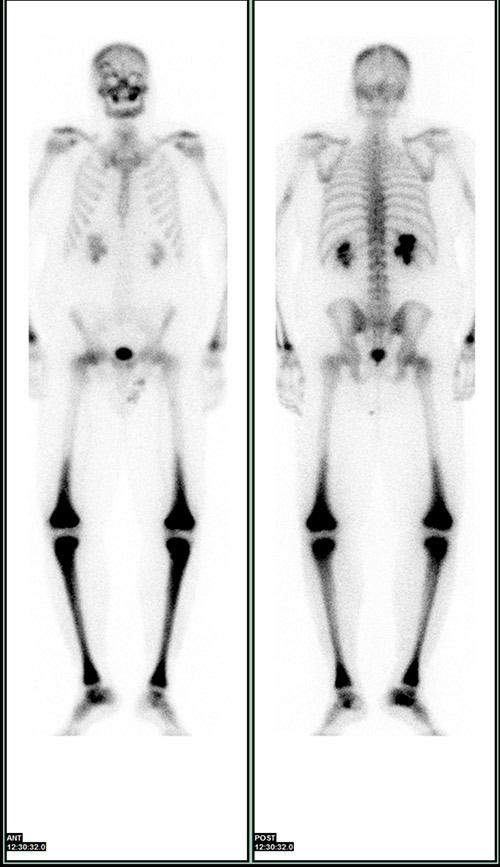

Røntgenundersøkelse av de lange rørknoklene viste symmetrisk utbredt sklerose i diafyser og metafyser, med utsparing av epifysene i radius, ulna, femur og tibia (fig 5). I tillegg var det tegn til periostitt, mest uttalt i femur og i tibia. Ved skjelettscintigrafi var det kraftig aktivitetsopptak i distale del av femur, proksimale og distale del av tibia, distale del av radius og i maksillen bilateralt (fig 6). Endokrinolog fant ikke holdepunkter for diabetes insipidus eller andre endokrine forstyrrelser.

Sykdommen rammer menn hyppigere enn kvinner, og gjennomsnittlig debutalder er 55 år (16 – 80 år) (5). Mange organer kan bli affisert av sykdommen (tab 1) (5, 6). Nesten alle pasienter med Erdheim-Chesters sykdom har affeksjon av skjelettet, men bare omkring halvparten har symptomer på dette og da som oftest som smerter i knær og ankler. Typiske radiologiske funn er bilateral og symmetrisk osteosklerose i diafysen og metafysen til de lange rørknoklene, oftest i underekstremitetene. 99technetiumskjelettscintigrafi og 18FDG PET-skann vil vise økt opptak i disse områdene (7) – (9).

Til forskjell fra langerhanscellehistiocytose ser man vanligvis ikke affeksjon av det aksiale skjelettet ved Erdheim-Chesters sykdom (7). Ved langerhanscellehistiocytose er det som regel osteolytiske lesjoner i skjelettet og sjelden affeksjon av de lange rørknoklene (7). Vår pasient hadde typiske funn i skjelettet, påvist ved både scintigrafi, røntgenundersøkelse og PET-skann.